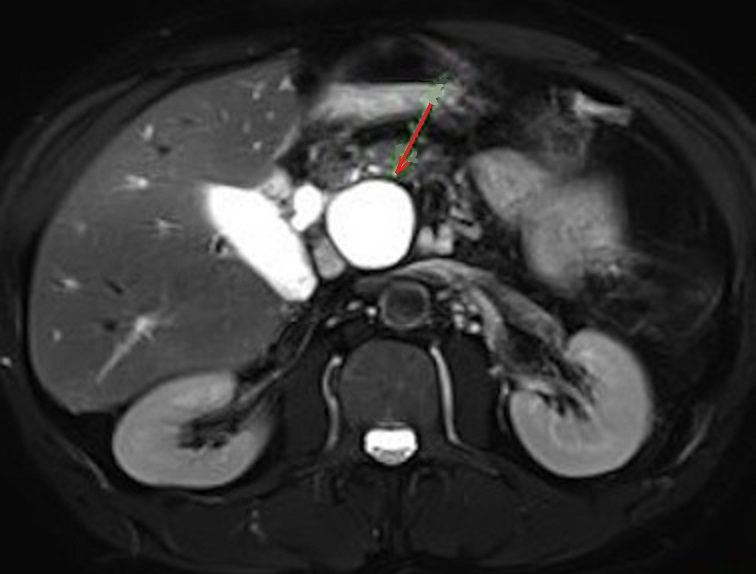

Meme cas en coupe IRM axiale

a ponderation T2 . Aspect radiologique lesionaire

est une kyste arrondie liquidienne de tres

hypersignal a bord lisse , regulier situe a la tete

du pancreas . Image IRM coupe axiale a ponderation

sur T2 |